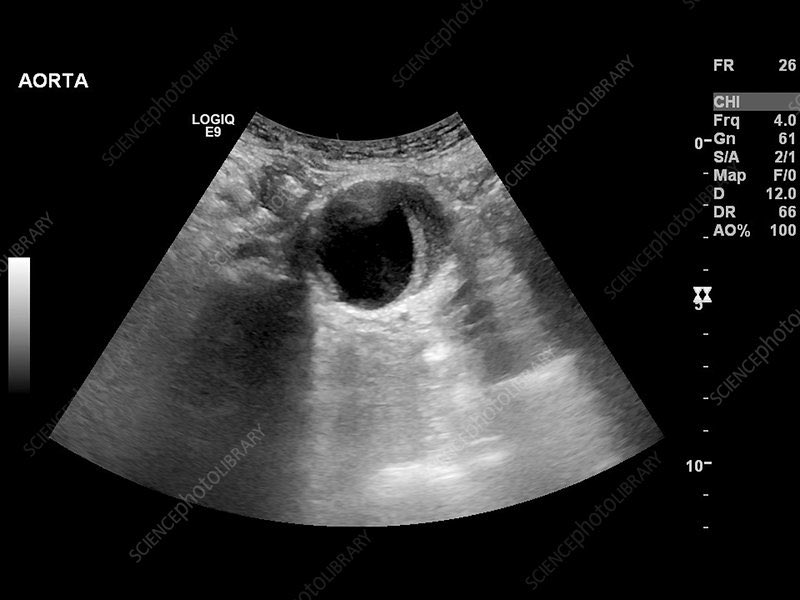

A case of Abdominal Aortic Aneurysm: Ultrasound This ultrasound image demonstrates a markedly dilated abdominal aorta, consistent with an abdominal aortic aneurysm (AAA). Ultrasound is the first-line imaging modality for AAA detection and screening due to its high sensitivity,…